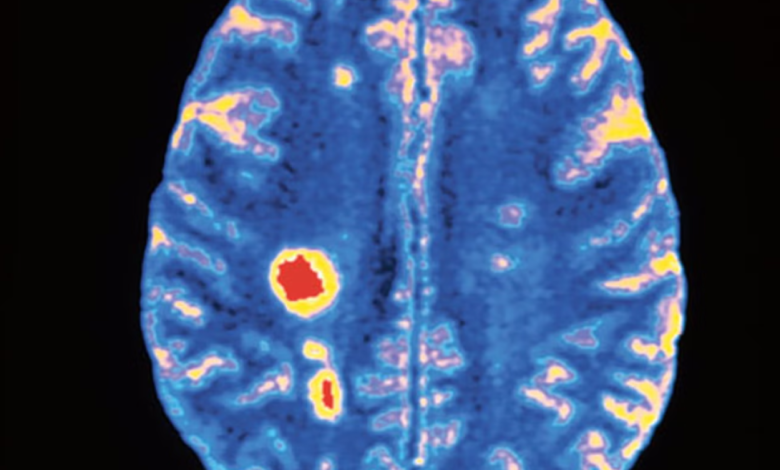

ويعرف عن مرض التصلب اللويحي أنه يؤثر في الدماغ والحبل الشوكي، مما يؤدي إلى ظهور أعراض على غرار المشكلات في الرؤية والصعوبات في الحركة أو الإحساس أو التوازن. وفي بعض الحالات، قد يتسبب في إعاقات خطرة. ووفقاً لـ”جمعية مرض التصلب اللويحي” الخيرية MS Society، هناك أكثر من 130 ألف شخص يعيشون مع هذا المرض في المملكة المتحدة، مع ظهور نحو 7 آلاف تشخيص جديد كل سنة.

وفي مرحلة مبكرة من التجربة التي قادها علماء من “جامعة كامبريدج” بالتعاون مع فرق من “جامعة ميلان بيكوكا” University of Milan Bicocca، ومستشفى البحوث “لا كاسا سولييفو ديلا سوفيرينزا” La Casa Sollievo della Sofferenza في إيطاليا، تضمنت العلاج حقن خلايا جذعية في أدمغة 15 مريضاً شخصت إصابتهم بمرض التصلب اللويحي الثانوي. [في سياق الكلمات السابقة، يقصد بالثانوي إنه ناجم عن سبب رئيس آخر على غرار التعرض لحادثة سير أو معاناة تأثيرات جانبية من أدوية أو حدوث جلطة في الدماغ وما إلى ذلك. في شكله العادي، يأتي التصلب اللويحي كمرض أساس في حد ذاته. وما زال السبب المحدد لحدوثه غير معرف تماماً].

يشار إلى أن الخلايا الجذعية المستخدمة في الدراسة جمعت من أنسجة دماغ جنين مجهض. وبعد العلاج، تتبع الباحثون مرضاهم لمدة 12 شهراً، ولم يلاحظوا حدوث أي وفاة لها صلة بالعلاج، أو أي آثار جانبية خطرة. وعلى رغم حدوث القليل منها، شمل بعض الالتهابات الطفيفة والارتعاشات العضلية، فإن الباحثين وصفوها بأنها “إما موقتة أو قابلة للانعكاس”. [القابلية للانعكاس تعني العودة إلى الحالة السابقة].